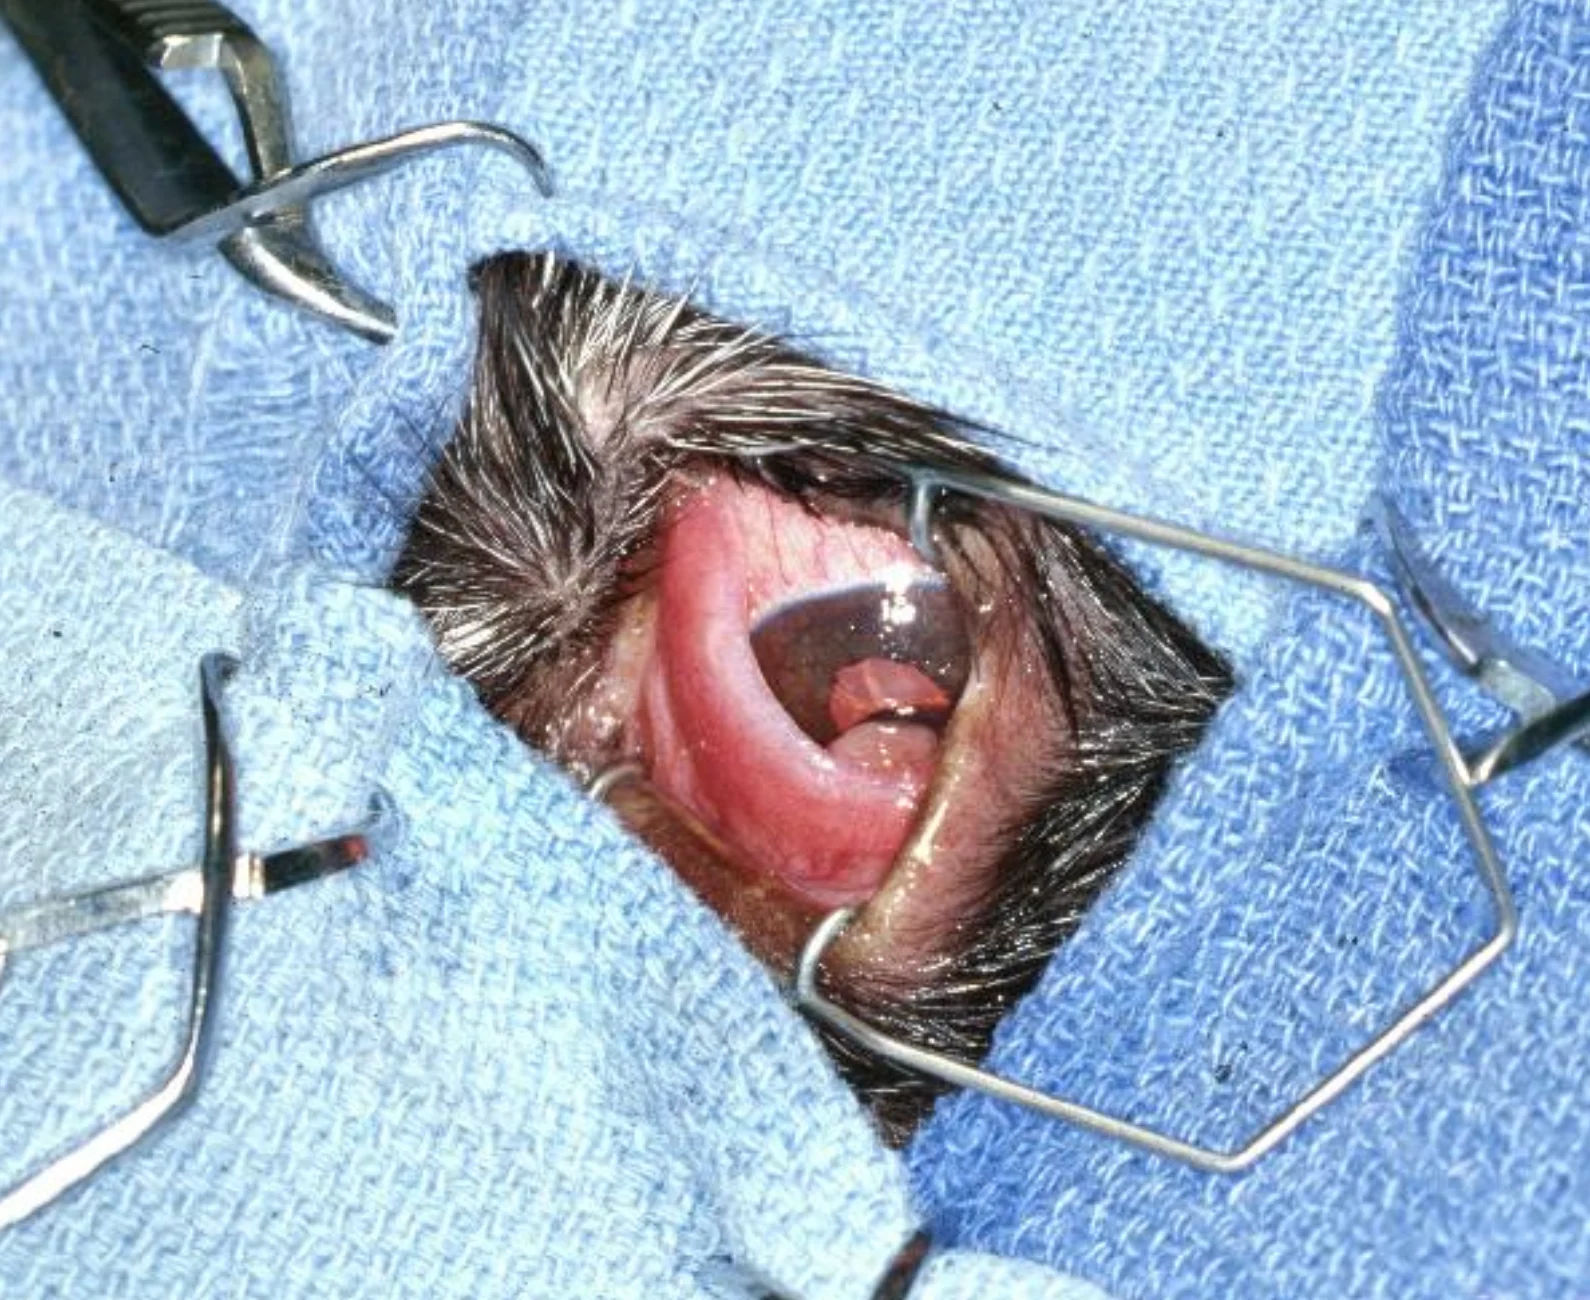

An adenoma of the third-eyelid gland protrudes above the dorsal margin of the third eyelid. The surgical site is prepared and draped. A wire lid speculum aids exposure of the nictitans during the procedure.